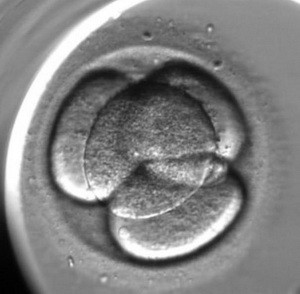

L’enregistrement du développement de l’embryon est le suivant :

La fin de la deuxième division (l’apparition du quatrième blastomère)

La simultanéité de la deuxième division (le moment entre l’apparition du troisième et du quatrième blastomère) Le commencement de la troisième division (l’apparition du cinquième blastomère)

La fin de la troisième division (l’apparition de huit blastomères)